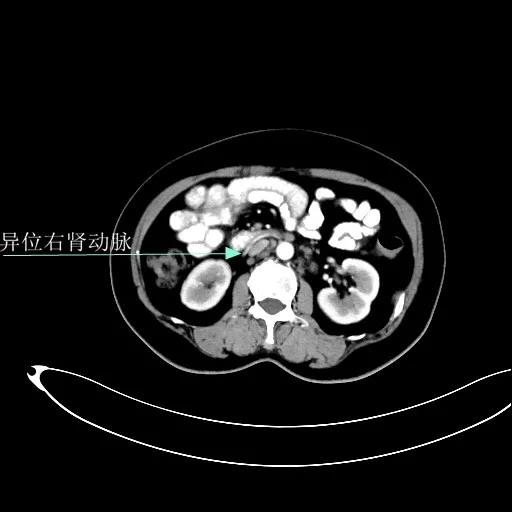

某患者因为“腹痛1周”而入院,外院B超提示子宫上方囊实性肿物,CT提示:左侧附件区占位,并盆腔及腹主动脉旁淋巴结转移。右肾动脉有右肾动脉及异位右肾动脉,其下均有肿大淋巴结。

肾血管总体变异率为35%左右,左侧型发生率为7.5%-23.5%,右侧型发生率为10%-25.3%,双侧型发生率为5.7%。肾动脉一般走行于肾静脉后方。本例异位右肾动脉由腹主动脉发出,经肾静脉前方走行进入右侧肾门,因此称为异位右肾动脉。不论哪个肾动脉分支,均为肾脏相应区域的终末供血动脉,如果发生病变或手术损伤,即可造成相应区域的缺血坏死,因此肾动静脉下淋巴结切除术过程中需警惕异位肾动脉或副肾动脉的存在。